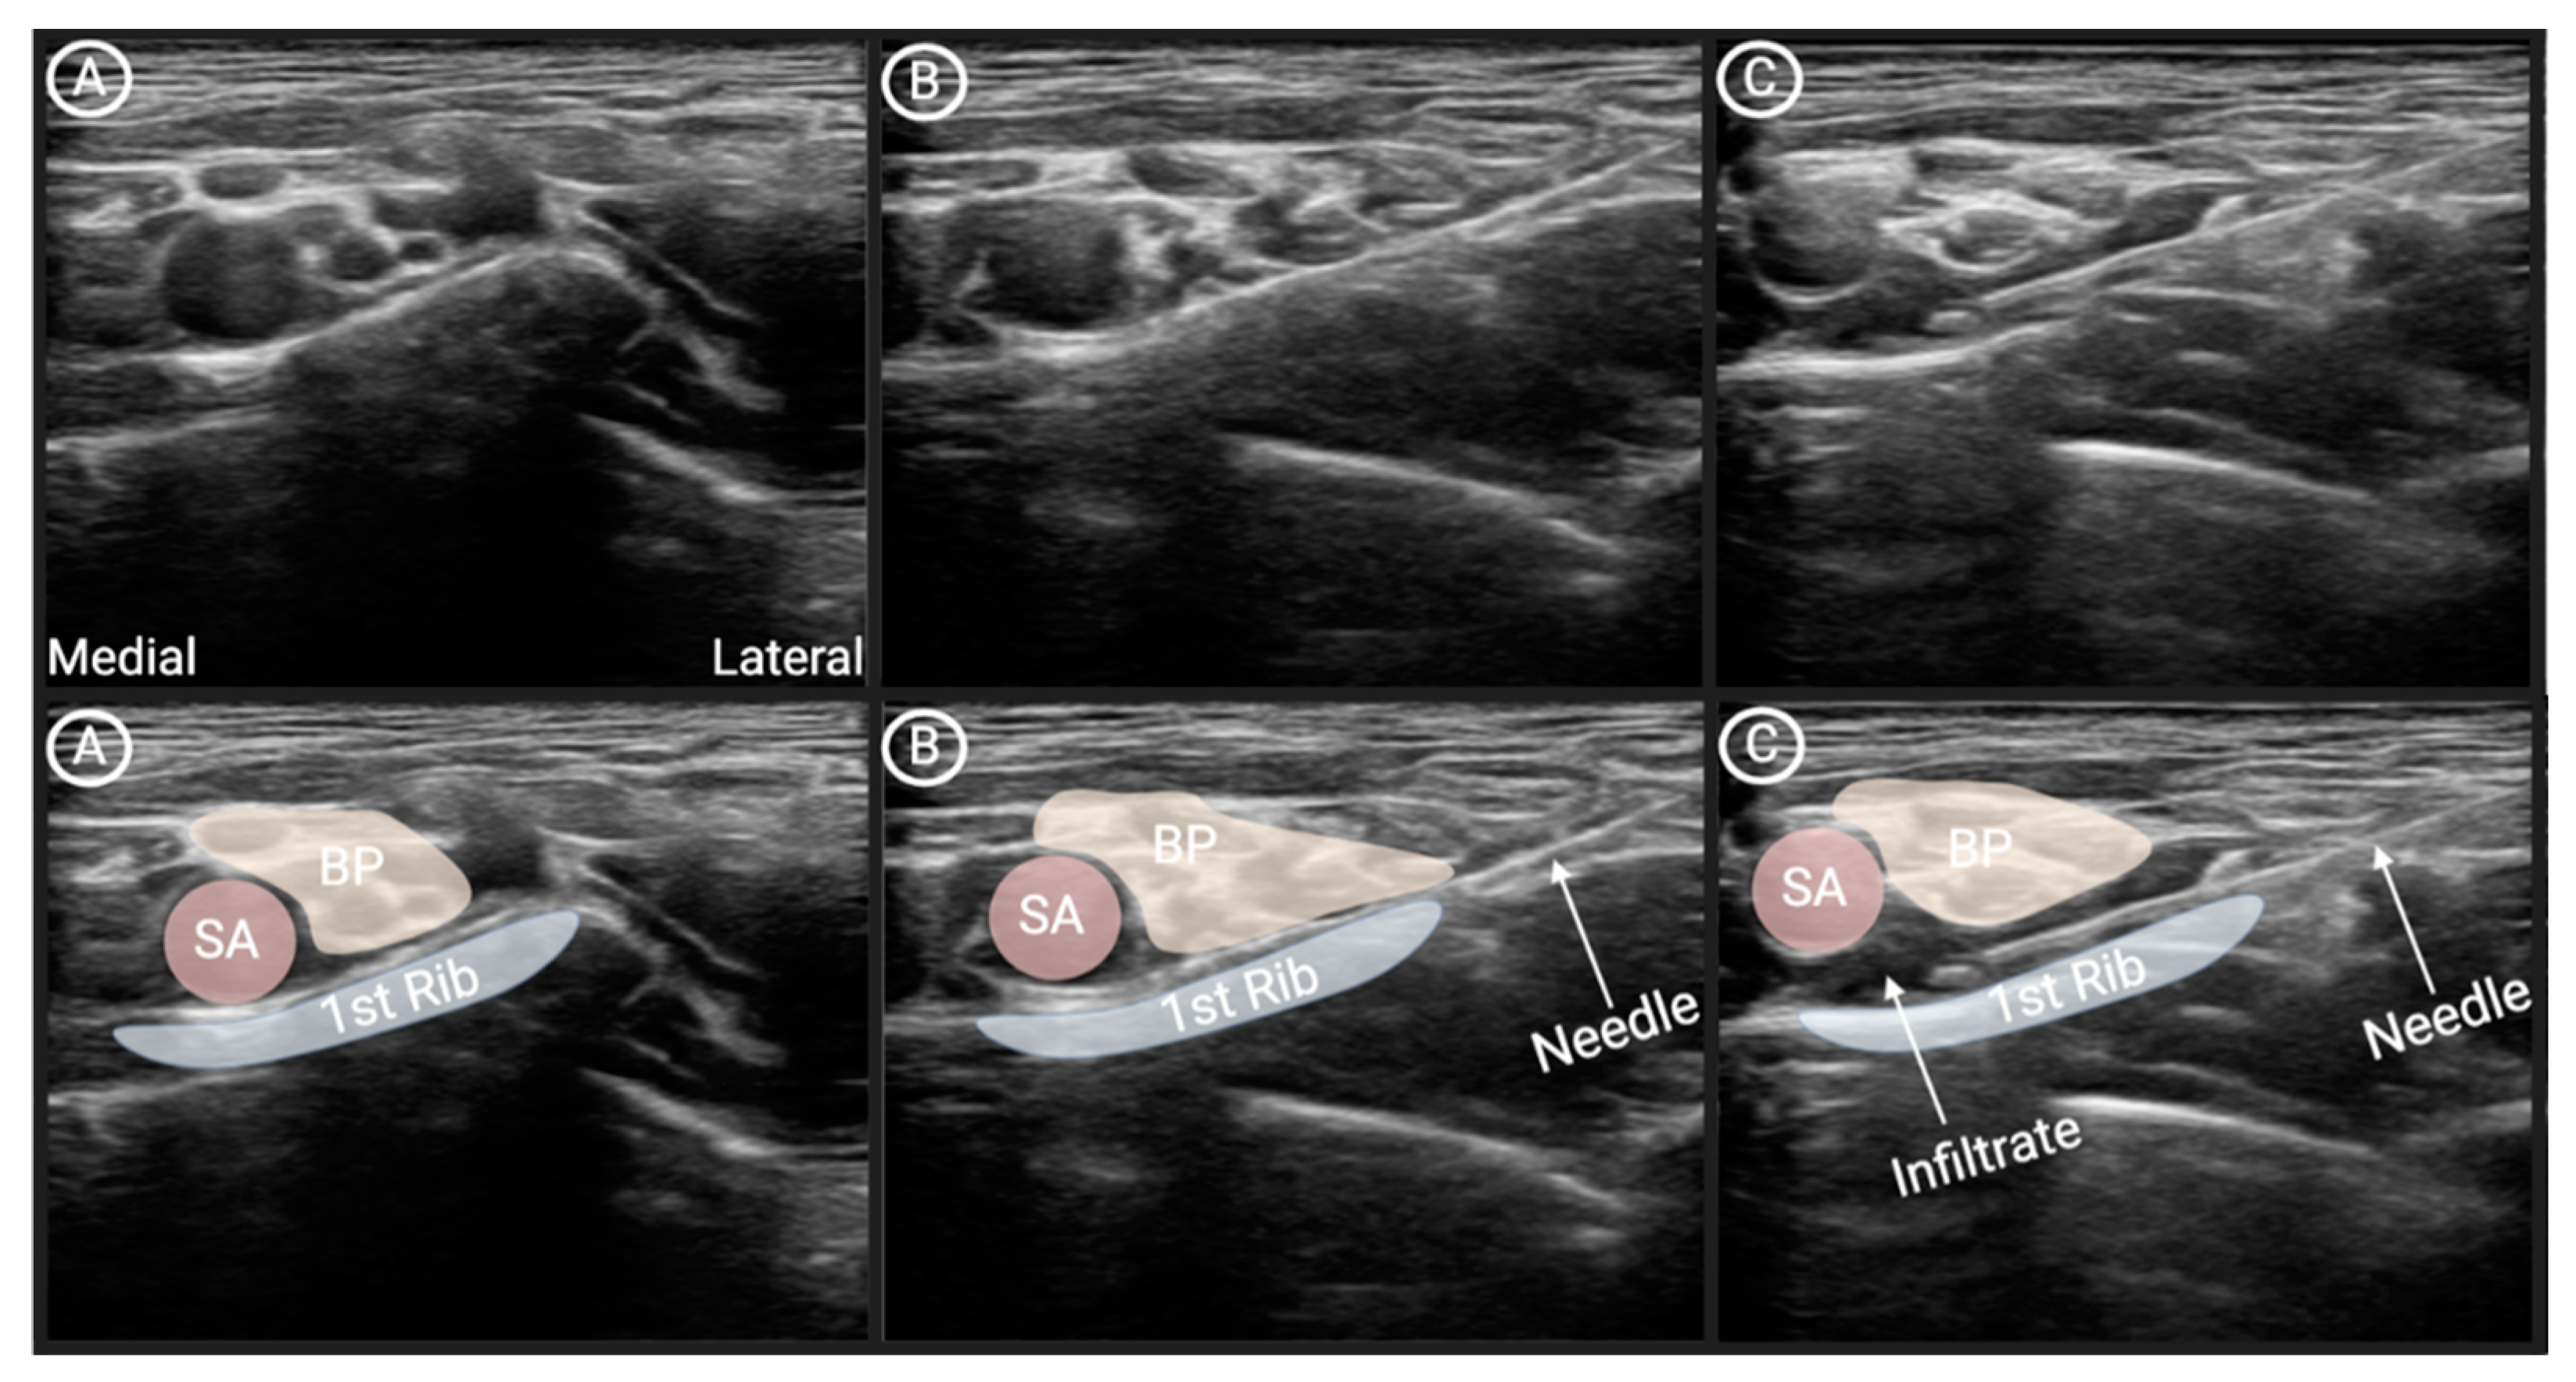

Figure 3. Image captures demonstrating the progression of supraclavicular nerve block procedure from patient one. A; Pre-procedural visualization of anatomy. B; Insertion of needle to the level of the ”cluster of grapes” in lateral-to-medial direction. C; Administration of anesthetic around the” cluster of grapes.” Abbreviations: SA, Subclavian artery; BP, Brachial plexus (“cluster of grapes”). Created in BioRender. Klinger, J. (2025) https://BioRender.com/vi3iu03.

Ultrasound Imaging: An ultrasound probe is placed on the patient's skin just above the clavicle to visualize the brachial plexus, which appears as a "cluster of grapes" at the root or trunk level. The brachial plexus lies adjacent to the subclavian artery and the first rib (Figure 3).

Needle Insertion: After identifying the correct anatomy, a fine needle is inserted in-plain, under real-time ultrasound guidance. The needle is advanced toward the brachial plexus, from lateral to medial, with the goal of depositing the local anesthetic medication near the nerve trunks, next to the subclavian artery, and 1st rib [12].